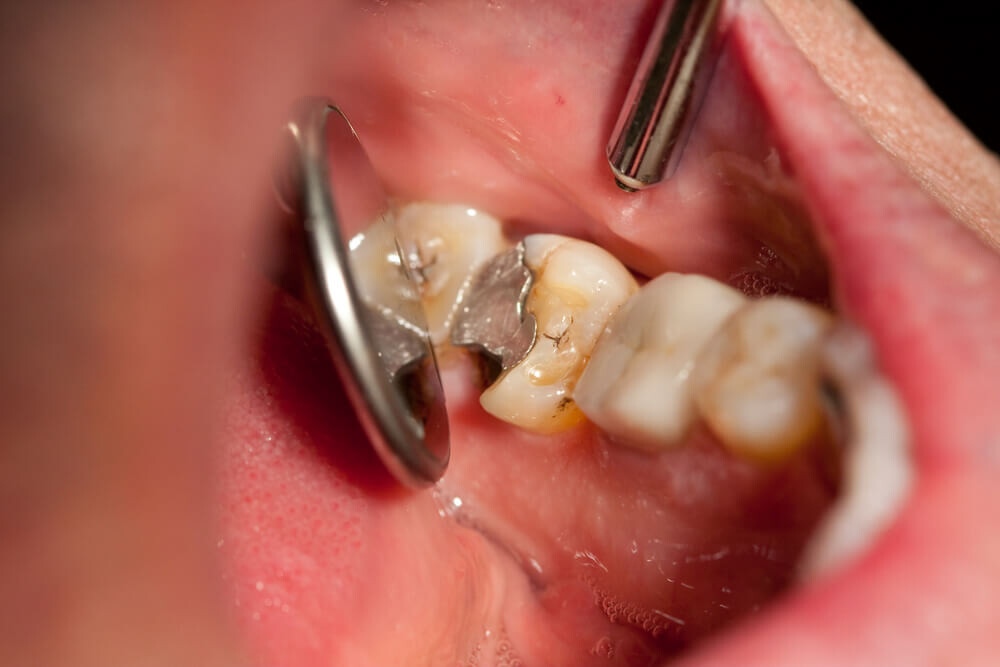

Tooth decay

As tooth decay progresses, it can reach the softer inner layers of the tooth, called dentin and pulp, resulting in sensitivity to hot, cold, or sweet foods and drinks and eventually leading to a toothache. If left untreated, tooth decay can result in an abscess, a painful infection at the root of the tooth that can cause severe pain and swelling. Adhering to your routine dental check-ups, practicing good oral hygiene, and eating a healthy diet can help prevent tooth decay and the resulting toothache.

A damaged filling

A damaged filling can cause toothache when the filling is no longer able to protect your tooth from external stimuli. When a filling is damaged, it can create an opening in the tooth, allowing bacteria to penetrate and cause an infection, leading to inflammation, swelling, and pain. Additionally, if you don’t replace the filling in time, it may cause your tooth to weaken or crack. A damaged filling may also cause sensitivity to hot and cold food and drinks.

Depending on the size of the cavity, you may be able to see evidence of it in your mouth. Cavities sometimes create visible holes in the teeth. They can also create stains that are black, brown or white on the surface of the tooth.

What should you do if you think you have a cavity? The first step is to see your dentist. Although cavities can be reversed in the early stages, by the time you are feeling discomfort or pain, only a dentist can treat them. An x-ray will be taken to determine how the cavity has progressed into the tooth. Depending on how severe the cavity is, you might need a filling to fix it. If the decay is very severe, the dentist might replace the tooth with a crown or perform a root canal.